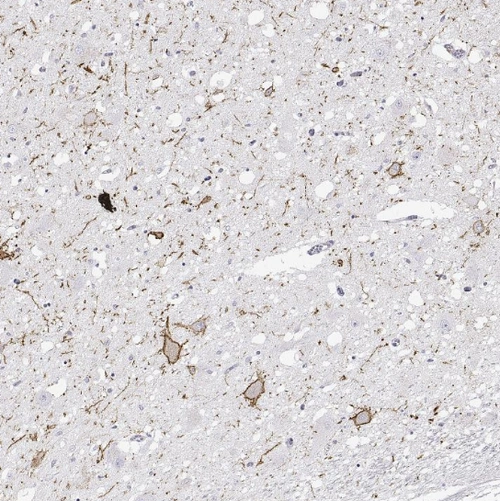

Immunohistochemical staining of human cerebral cortex, hypothalamus, lymphoid tissues and pancreas using Anti-CALCR antibody HPA028962 (A) shows similar protein distribution across tissues to independent antibody HPA061428 (B).